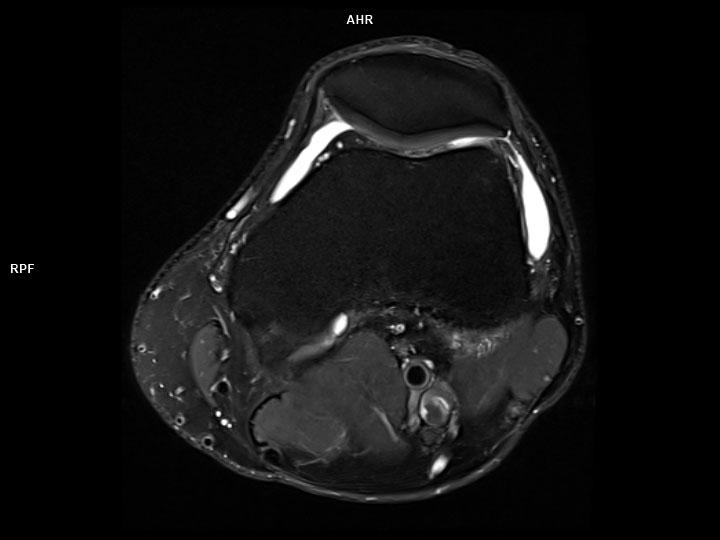

Axial PD FS-MAGNETOM Lumina

Axial PD FS-MAGNETOM Lumina/Coil-Knee 18/Resolution-384/Scan Time-1:38/Aceleration-p2